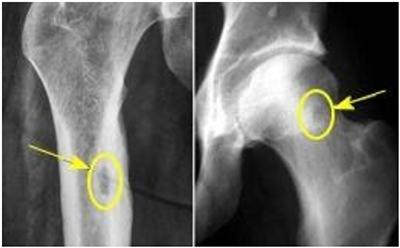

Для установления диагноза необходимо провести рентгенограмму или компьютерную томографию поражённой области кости:

- рентгенограмма бедренной кости;

Рентгенография бедренной кости Рентгенологическое исследование костно-суставной системы нижних конечностей предназначено для обнаружения различной патологий, в том числе и травматического ге.

Рентгенография является основным и наиболее информативным методом диагностики остеомы, на снимках опухоль выглядит как образование с высокой плотностью и четкими контурами, превышающими плотность окружающей костной ткани. Губчатая остеома на рентгеновских изображениях демонстрирует неоднородную структуру, с чередующимися зонами разрежения и уплотнения (см. изображение ниже). При малых размерах опухоли может быть назначен компьютерный томограф. При необходимости проводят гистологическое исследование, при котором выявляют характерные изменения архитектуры компактной кости, практически отсутствие каналов остеонов и сужение сосудистых каналов.

Для диагностики используется рентгенография, на которой выявляется овальной формы очаг деструкции костной ткани с чёткими контурами с зоной остеосклероза вокруг очага за счёт периостальных/эндостальных изменений (фото ниже).

На начальном этапе формирования опухоли четко выделяется граница между центральной зоной и ободком, которая постепенно исчезает по мере минерализации опухоли. Основная сложность в диагностике остеоид-остеомы заключается в её малых размерах, которые часто не превышают 1,5 см. Для более точного определения характера поражения и визуализации области интереса рекомендуется выполнять компьютерную томографию или МРТ с использованием тонких срезов для получения изображений высокого качества, так как удаление опухоли проводят под контролем лучевых методов.